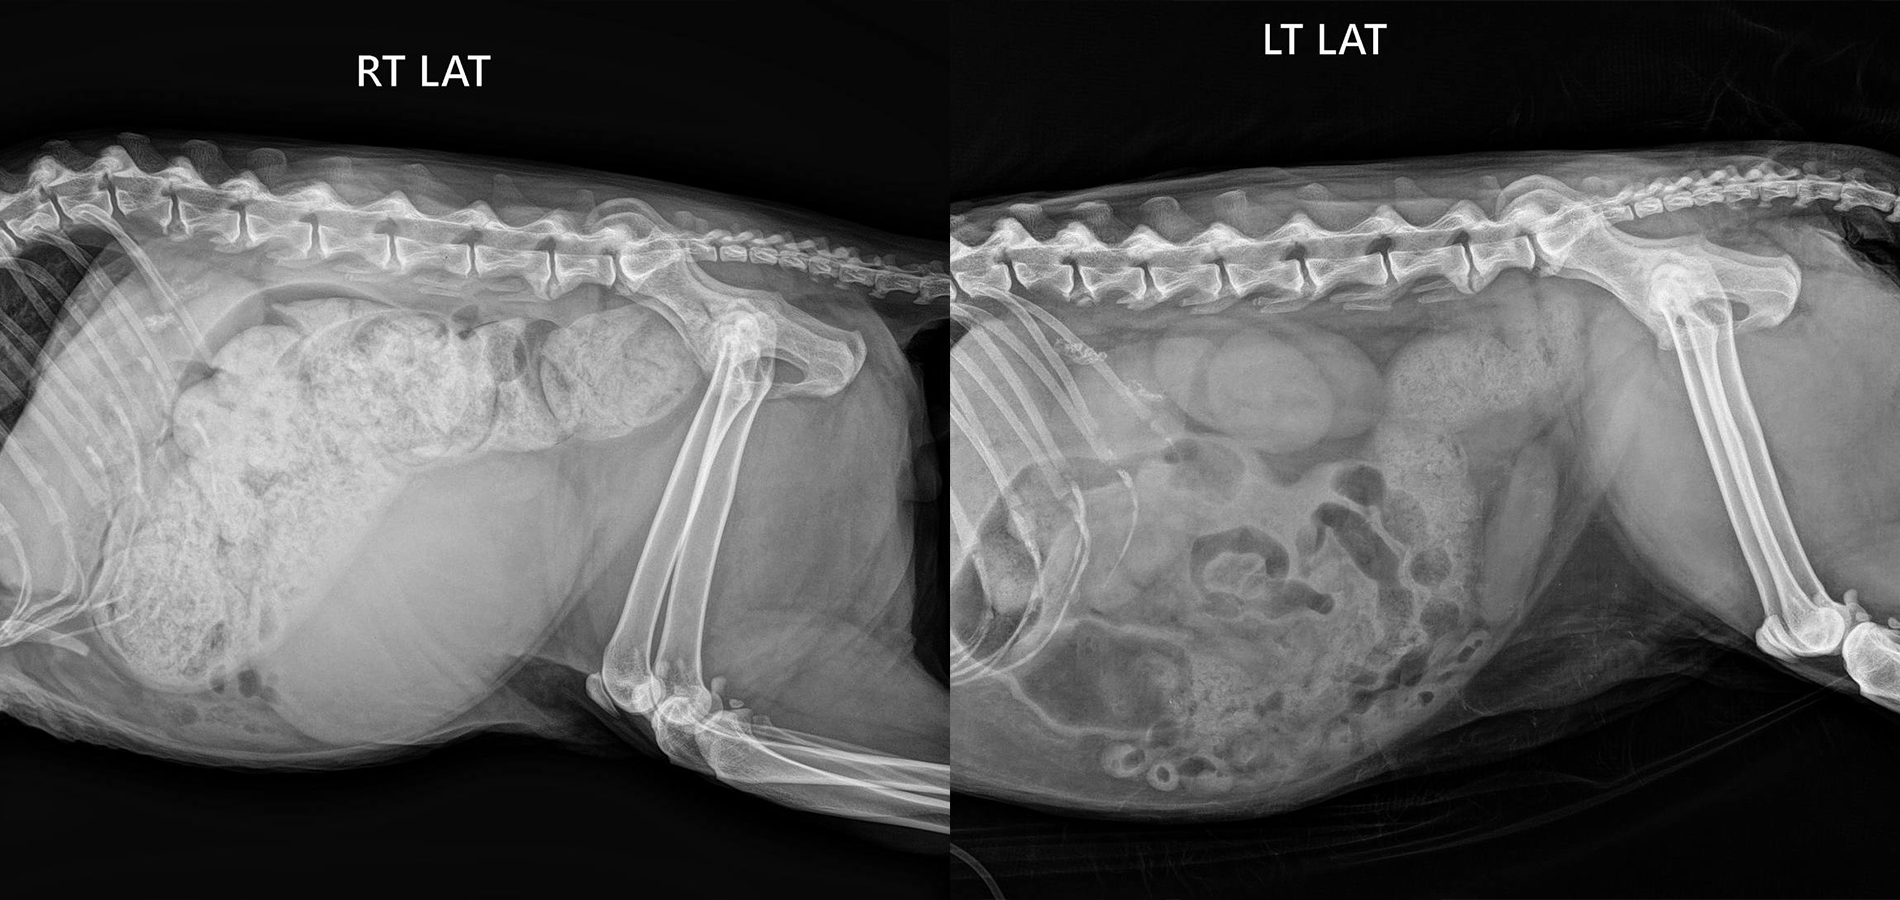

(кот 3,5 года: отсутствие стула в течение 5-ти дней)

Основной метод диагностики копростаза – это рентген брюшной полости. Рентгенография позволяет определить наличие переломов, аномалий в строении, наличие инородных тел в просвете кишки, визуализировать рентгеноконтрастные новообразования в брюшной полости и кишечнике.